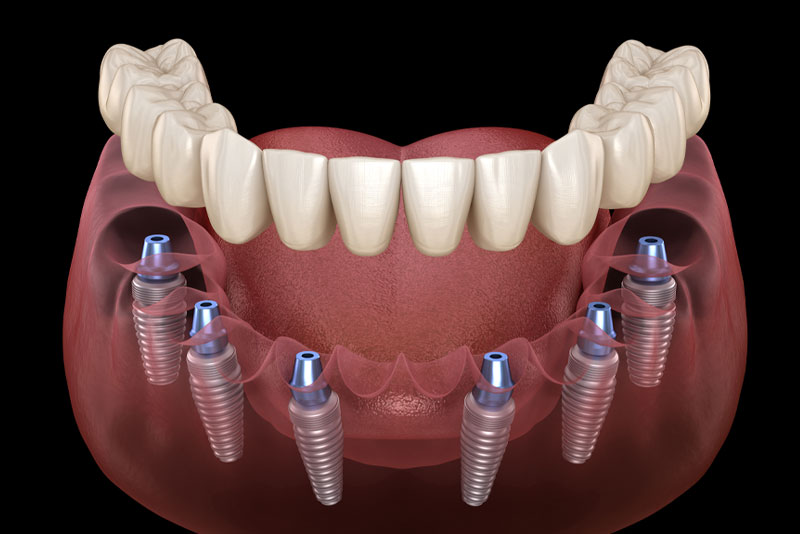

With Digital Smile Design, Can I Get Customized Full Mouth Dental Implants In Ocala, FL?

When people with a full arch of missing teeth want to get customized full mouth dental implants in Ocala, FL, they should get treated with